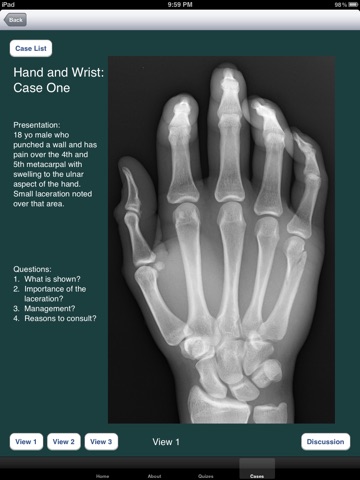

The application is one to use to learn skills related to the emergent-based diagnosis and care of orthopedic injuries. There are online tests associated with the application in order for a learner or instructor to gauge pre/post knowledge base, identify weakness, and measure competence. Some of the goals behind the app include: learning interpretation of plain films, appropriate care of orthopedic injuries, diagnosis and care of associated injuries, teaching management strategies, and uniform means of assessment through the online testing.